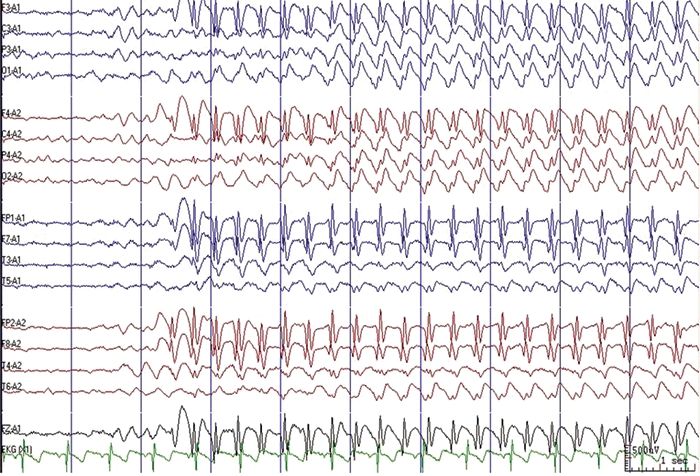

TYPICAL ABSENCE SEIZURE Childhood Absence Epilepsy (CAE) - Petit Mal Epilepsy - Pyknolepsy Childhood Absence Epilepsy | Epilepsy Foundation Frontiers | Absence Seizure Detection Algorithm for Portable EEG Devices | Absence Seizure Eeg